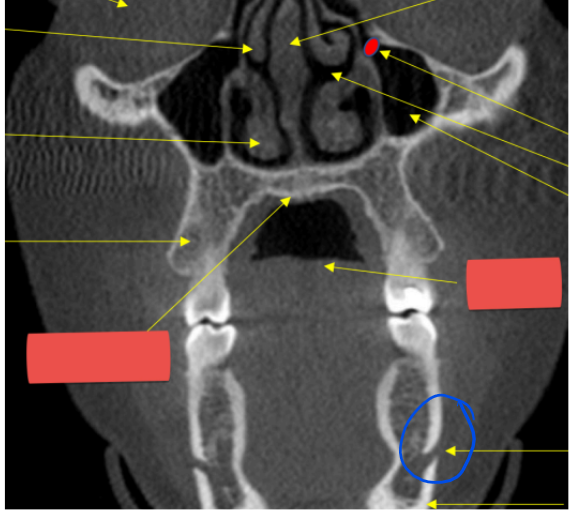

red - zygomatic process of maxilla

blue - zygoma

Negative angulation of pano x-ray source results in objects appearing

Higher

Bc of occipital bone